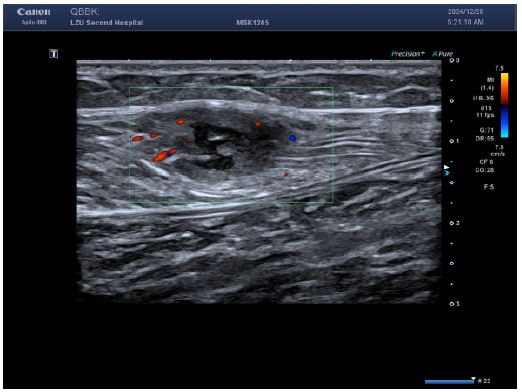

Imaging studies (Figures 1-4):

Figure 2: Color Doppler flow imaging showed a small amount of short rod-shaped blood flow around the lesion.